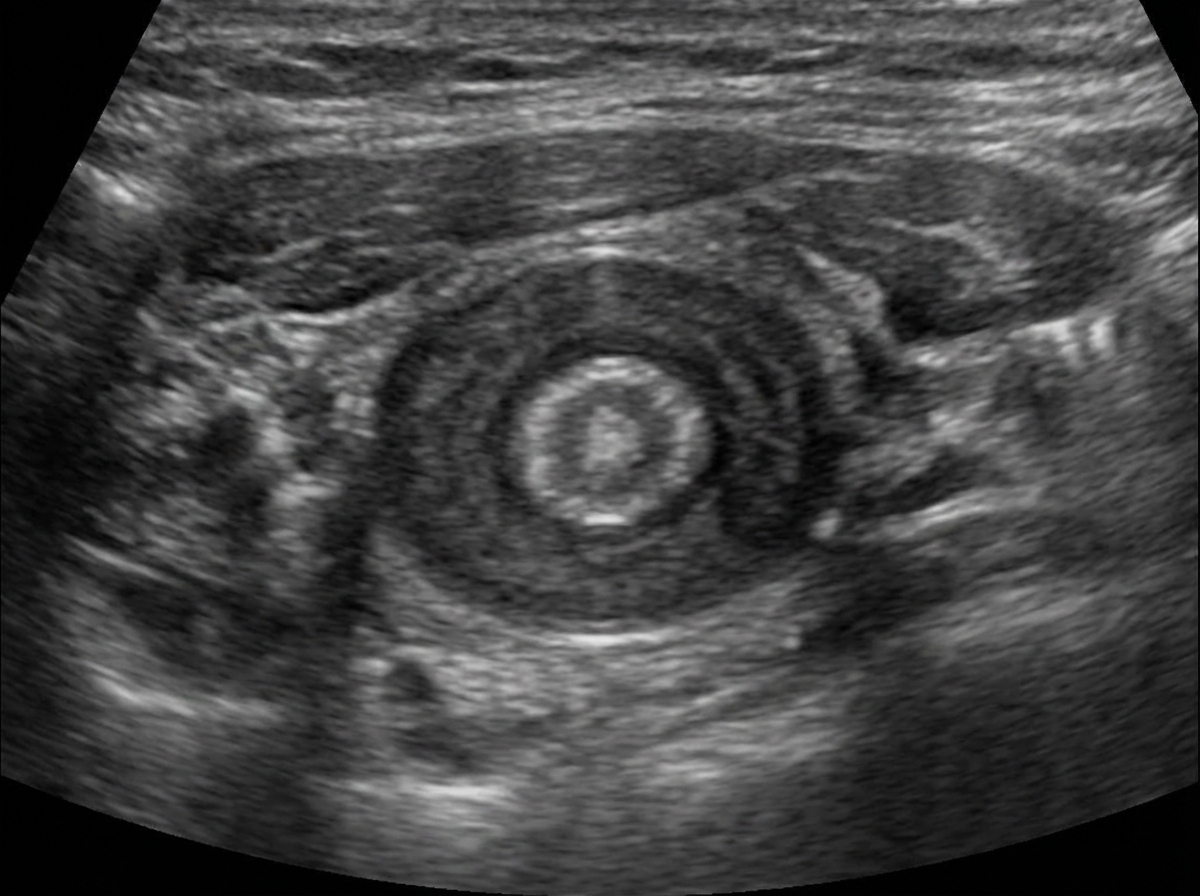

A 6-week-old child with a history of vomiting undergoes an ultrasound, which shows an antral nipple sign or target sign, as shown in the image. What is the diagnosis?

Explanation: ***Congenital pyloric stenosis*** - The ultrasound findings of an **antral nipple sign** and **target sign** are classic indicators of **hypertrophic pyloric stenosis**. - This condition presents with **projectile vomiting** in infants, typically between 3-6 weeks of age, due to hypertrophy of the pyloric muscle. *Umbilical hernia* - An **umbilical hernia** is a protrusion of abdominal contents through the umbilical ring. It is usually diagnosed clinically and presents as a bulge, not with vomiting. - Ultrasound for an umbilical hernia would show bowel loops or omentum protruding through the abdominal wall defect, not the specific pyloric signs described. *Small bowel obstruction* - While small bowel obstruction can cause vomiting, the ultrasound findings would typically show **dilated loops of bowel** and a **transition point**, not an antral nipple or target sign specifically at the pylorus. - Other clinical features, such as abdominal distention and absence of stool, would also be more prominent. *Jejunal atresia* - **Jejunal atresia** is a congenital anomaly where part of the jejunum is underdeveloped or absent, leading to a complete obstruction. - Ultrasound would reveal **dilated loops of small bowel**, typically without peristalsis past the obstruction, and polyhydramnios antenatally, but not the specific pyloric ultrasound signs. *Duodenal atresia* - **Duodenal atresia** is a congenital obstruction of the duodenum that typically presents with bilious vomiting soon after birth. - The characteristic ultrasound finding is the **"double bubble" sign**, representing a distended stomach and proximal duodenum, not the target or antral nipple sign seen at the pylorus.